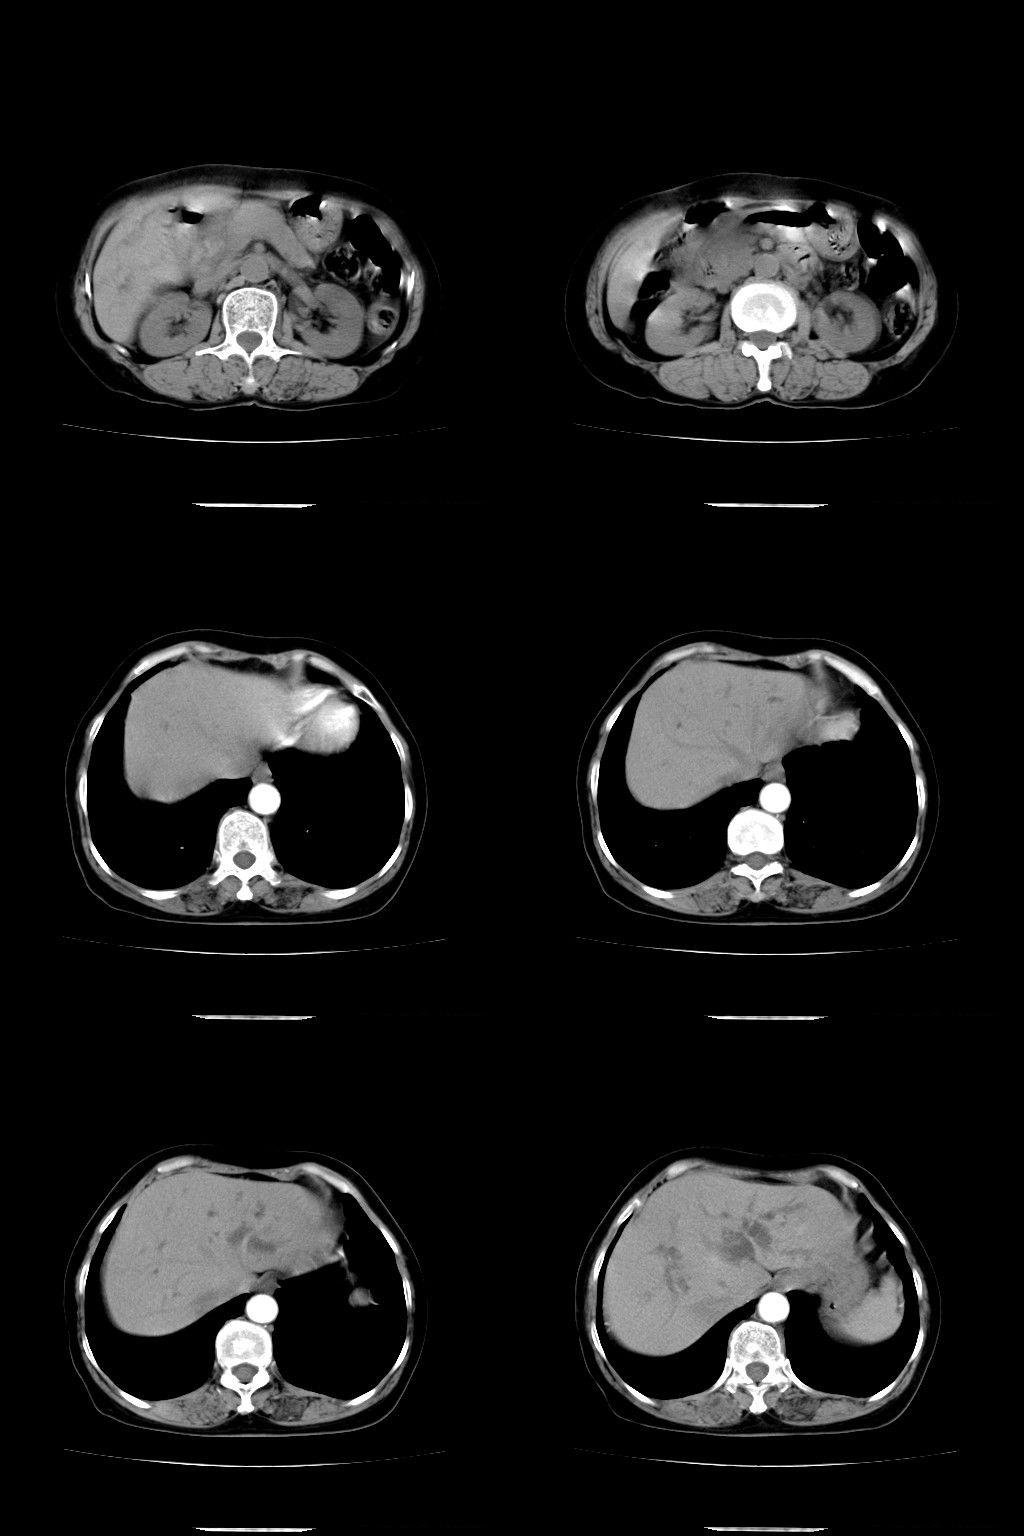

以下是引用随光逐影在2009-1-22 9:27:00的发言:[br]1)考虑胆囊癌侵犯肝脏。2)肝总管及胆总管多发性结石并肝内、外胆管扩张。

以下是引用余辉在2009-1-22 8:49:00的发言:[br]平扫肝内胆管扩张,右肝前叶球形低密度影,边缘较清楚,胆囊壁增厚,内可见较大高密度影,胆总管内亦可见高密度影,胰头区结构欠清。[br]增强动脉期见右肝前叶球形变灶明显增强,边缘见环状低密度区。胆囊见高密度影无增强,胆总管明显扩张,内见块状高密度影,周围环以低密度区,边界清楚。[br]静脉期见右肝前叶病灶持续增强,密度较动脉期增高。[br]考虑1胆囊及胆总管结石伴梗阻性胆系扩张,胆囊胆管炎。[br] 2右肝前叶占位性病变,强化规律符合胆管细胞癌,建议结合其他检查协诊